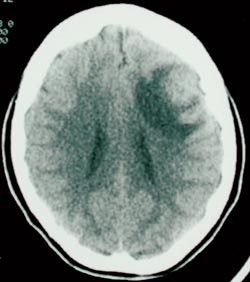

Laboratorieprøver viste Hb 9,5, hvite blodceller 7,6, CRP 29, SR 36. Elektrolytter, blodsukker, lever- og nyrefunksjonsprøver var normale. HIV-test negativ. CT caput (fig 1) viste 2 cm stor kontrastoppladende ringlesjon med ødem frontotemporalt på venstre side. Man mistenkte tumor, eventuelt abscess, og det ble startet behandling med antibiotika, fenytoin og deksametason.